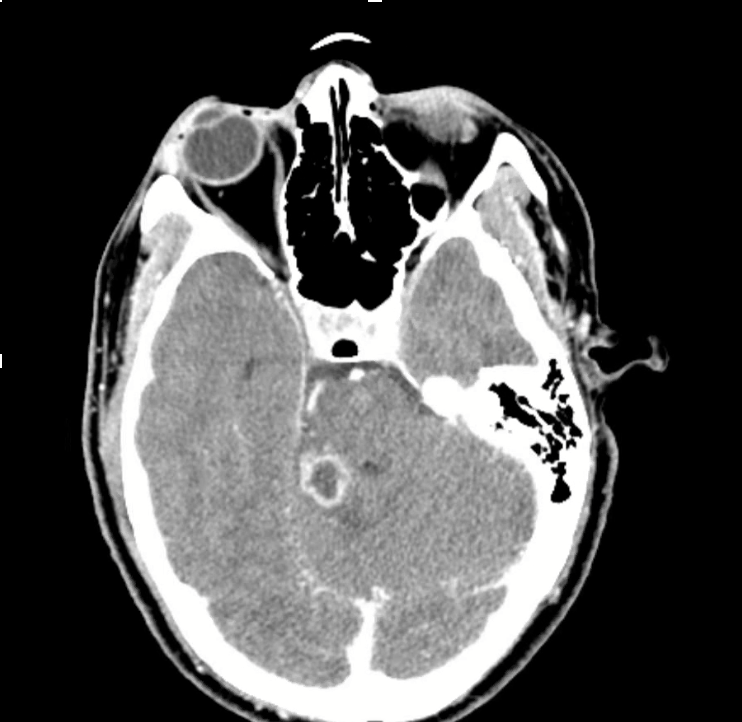

3) Neuro findings—ring-enhancing lesions

• Differential: septic emboli/abscess, nocardia, fungal, TB, parasites, metastases, vasculitis, sarcoid.

• Partner with neuroradiology for pattern nuances; treat seizures but keep searching for the unifying diagnosis.

• Path: TTF-1+, CK7+, napsin A → pulmonary adenocarcinoma with a fusion driver.

• Therapy: Targeted TKI (crizotinib) → dramatic radiographic response of miliary lung disease and CNS lesions.

• Teaching point: even “miliary TB-like” lungs + CNS lesions in a 20-something can be driver-positive lung cancer—don’t let age or pattern blind you.